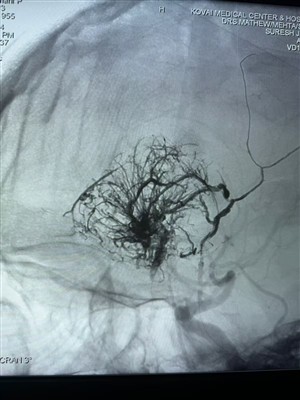

Trường hợp đầu tiên về khối u mạch máu được báo cáo ở Ấn ĐộVui mừng chia sẻ trường hợp khối u giàu mạch máu đầu tiên được thực hiện ở Ấn Độ. Nó đã được điều trị bằng Hệ thống thuyên tắc chất lỏng dung nham của NeuroSafe Medical Co., Ltd.. Cảm ơn bác sĩ Mat...

Hơn -